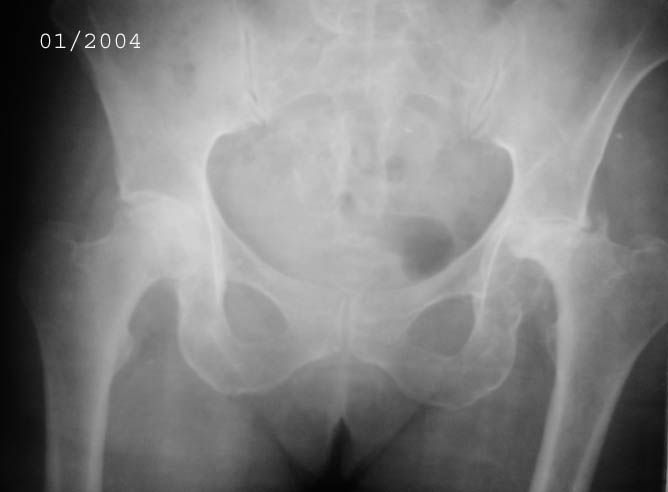

Уважаемые коллеги! Прошу Вас оказать консультативную помощь. Женщина, 44 года, инвалид 3 группыДиагноз: СКВ, асептический некроз головок обеих бедернных костей, двусторонний артроз 3-4 ст., болевой синдром, приводящая контрактураправого тазобедренного сустава, хронический волчаночный гепатит, спленомегалия, анемия, СКВ с 2002 года (подтверждена наличием lupus-клеток), получала специфическую терапию, медрол 16 мг/сут. Боли в левом тазобедренном суставе появились в сентябре 2003 года. Динамика отражена на рентгенограммах. В марте 2004 года - синдром Мэллори-Вейса, кровотечение остановлено эндоскопически. Объективно: кожа бледная, пастозность, отечность лица, высыпания на лице практически отсутствуют. Печень +6 см, селезенка не пальпируется. АД140/80, пульс 100, дыхание 15.

Ходит с тростью, хромота. Объем движений в суставах: справа - сгибание 90, разгибание 170, отведение 0, приведение 20, внутренняя ротация 15;слева - сгибание 90, разгибание 180, отведение 0, приведение 20, внутренняя ротация 0, наружная ротация 20. ЭКГ - отклонение ЭОС влево, гипертрофия левого желудочка, дистрофические изменения миокардаОбщий анализ крови: Э. 3,6, Hg 100, цп. 0,83, л.7,3, э.1, п.3, с.72, л.19, м.5, СОЭ 5 Общий анализ мочи: объем 120,0, уд.вес 1008, желтый, р-ция кислая, сахар/белок/цилиндры нет, эпителий и эритроциты единичные, Л.1-2, солиоксалатовые в небольшом к-ве. Биохимический анализ крови Билирубин 11,5 ммоль/л (прямой 0, непрямой 11,5), АСТ 0,24, АЛТ 0,61, протромбиновый индекс 100, рекальцификация 150, фибриноген 1,99,толерантность 8, фибринолитическая активность 240, общий белок 74,3, сиаловые кислоты 250 ед., С-реактивный белок 0. Пациентка желает выполнить тотальное эндопротезирование. Допустимо ли выполнение подобной операции? При каких условиях, дополнительной терапии? Особые предоперационные мероприятия? Личный опыт? Комментарии?Мнения? Заранее благодарю!!! С уважением, А.В.Владзимирский Донецкий НИИ травматологии и ортопедии